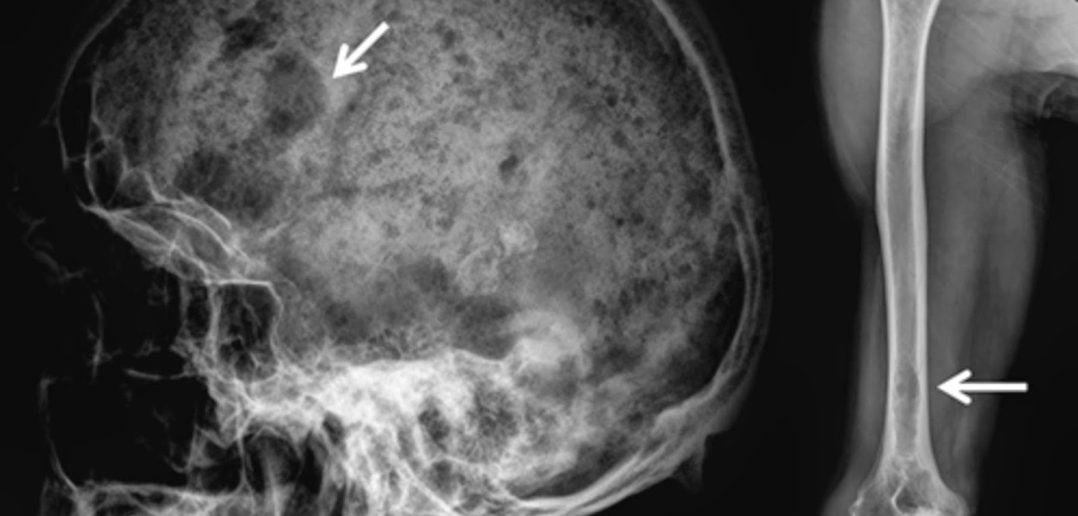

Mielomul Multiplu reprezinta un tip de cancer de sange care se manifesta prin multiplicarea necontrolata a plasmocitelor (un tip de leucocite) de la nivelul maduvei osoase.

Diagnosticul de certitudine pentru mielomul multiplu se stabilește de cele mai multe ori atunci când aceasta afecțiune este deja intr-un stadiu avansat, cu o simptomatologie importanta, fapt ce conduce la scăderea șanselor de supraviețuire. Din păcate, Romania este in urma tarilor dezvoltate cu aproximativ 5-6 ani in materie de acces la tratamente inovatoare și diagnosticare precoce a acestei afecțiuni oncologice. Acest decalaj trist este confirmat zilnic prin decesele care pot fi evitate. În contextul Planului Național de Combatere și Control al Cancerului, in componenta dedicata mielomului multiplu, trebuie sa se reglementeze in regim de urgenta modul in care investigațiile medicale specifice diagnosticării precoce a acestei afecțiuni sa se realizeze in mod gratuit, sa devina un mecanism de screening dedicat. Accesul la terapii inovatoare (mai ales pentru pacienţii cu acest tip de cancer care nu mai au alternativă terapeutica) sa se realizeze in mod constant. Pe aceasta cale, facem un apel către toți cei implicați in procesul de decizie, sa intreprindă toate masurile necesare, pentru ca noi, pacienţii cu cancer, sa avem o șansă la viață. FABC se implica activ in susținerea pacienților cu cancer, prin intermediul CallCenter-ului de suport gratuit pentru pacient – 021 253 0591 – prin care pacienţii pot beneficia de informații medicale generale, îndrumare și navigare prin sistemul de sănătate, consiliere psihologică gratuită, consiliere de nutriție si dietoterapie – a declarat Cezar Irimia, președinte Federația Asociațiilor Bolnavilor de Cancer Planul Național de Combatere și Control al Cancerului a fost lansat în 19 ianuarie 2022 și